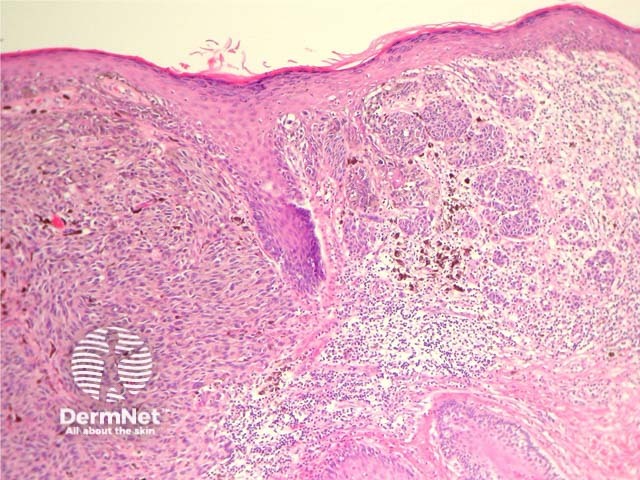

Most melanomas have an initial radial growth phase within the epidermis and sometimes within the papillary dermis (figure 1, 2), which may be followed by a vertical growth phase with deeper extension (figures 3, 4). The exception to this is nodular melanomas, which either skip the radial growth phase or the radial phase is rapidly overrun by the vertically growing tumour. It is also possible that they arise within dermal melanocytes. It has been proposed that lesions in the radial growth phase are incapable of metastasis, however there are numerous examples of thin melanomas that have behaved aggressively, even without convincing evidence of vertical growth.

Figure 1

Figure 2

Figure 3

Figure 4